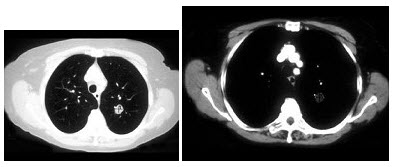

21、单项选择题

女,64岁,发热、咳嗽1周。胸部CT扫描如下图。

患者抗炎治疗2周后,行胸部CT增强扫描检查,如下图,则最具诊断意义的征象为()

A.多发钙化灶

B.多发含气囊腔

C.多发短毛刺

D.供血动脉起自降主动脉

E.供血动脉起自腹主动脉